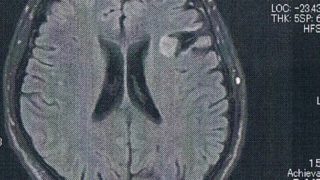

GLIOMA:手術後126ヶ月目の検査

手術から10.5年が経過した。半年ごとの定期検査です。検査概要びまん性星細胞腫グレード2(悪性転化しやすい腫瘍)MRI検査: 造影剤なし / 造影剤あり造影剤ありの場合:4時間前から絶食し、MRIの1時間前に血液検査を済ませる。診断結果MR...